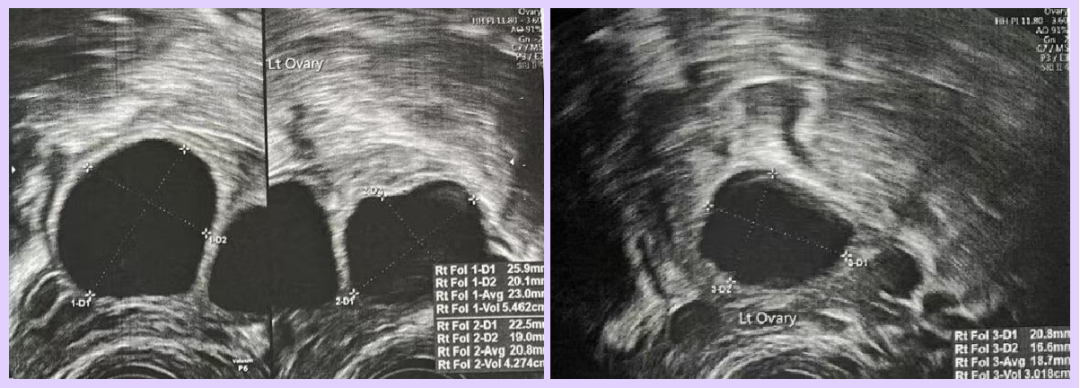

- Day 9 of Stimulation (Thailand)

- Ultrasound Findings:

- Right ovary: 1 follicle (16mm)

- Left ovary: 3 follicles (23mm, 20mm, 18mm)

- Day 17 of Menstrual Cycle (Thailand)

- Ultrasound Findings: Endometrial thickness 11 mm

| 5 weeks | 41,759 | 15.06 | Gestational sac: 24×18×10 mm, yolk sac: 3.3 mm, no fetal heartbeat or embryo visible |

| 6 weeks | – | – | Gestational sac: 30×22×19 mm, yolk sac: 3.1 mm, fetal heartbeat and embryo (5×3 mm) visible |

▲ Ms. A’s ultrasound image